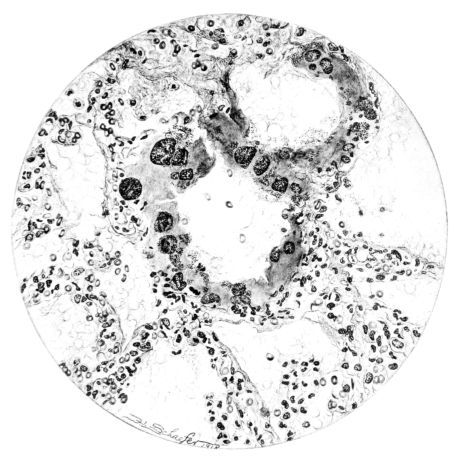

FIG. VIII. AUTOPSY NO. 97. ALTHOUGH THE EPITHELIUM IS STILL VISIBLE AS A HYALINE BAND LIFTED FROM THE UNDERLYING MUCOSA, BOTH MUCOSA AND SUBMUCOSA ARE INVOLVED IN A NECROTIZING PROCESS. BACTERIA ARE ABUNDANT IN THE DEAD TISSUE.

15There is considerable evidence to support the view that the disease spreads from bronchus to bronchus, and in keeping with this view, various stages in the inflammatory processes are more readily determined in these smaller structures than in the trachea. Furthermore, it must be emphasized that even the mildest and the most extreme of these stages are not infrequently encountered in the same lung. The earliest lesion is manifested by an increased homogeneity of the protoplasm of the epithelial lining of the bronchus. The cell protoplasm loses its normal granulation and the nucleus, somewhat darker than usual, becomes conspicuous on a red base (Fig. V). In the lumen of such a tube a serous exudate, perhaps mixed with mucus, is encountered, and there is some spreading apart of the surrounding muscular tissue with engorgement of the vessels. This picture merges gradually into one where the epithelium appears as a homogeneous, red-staining ribbon, devoid of nuclei, often exfoliated, in part at least, from the underlying submucosa (92). The change is traceable through the larger bronchi, even to the ducti alveolares, and not infrequently, bacteria, either as a diffuse, minute dotting or in the form of circumscribed, colony-like formations, are spread through the red, ribbon-like strand (Fig. XVI). With the exfoliation of the epithelial lining, the submucous vessels become more and more conspicuous and may bulge into the lumen of the tube (Fig. VI). That they actually weep into the lumen is proved by the presence of red blood cells in the exudate, now rich in mucus, broken-down nuclei, and desquamated cells. The necrotizing process may not extend deeper than the epithelial lining as is the status described above (140, 162), but it also frequently involves the underlying submucous and muscular layers, so that these lose their identity and stand out as homogeneous masses, in which fragmented nuclei and bacterial accumulations are prominent. Such deeper necrotizing areas may be focal (Fig. VII), or may involve the entire circumference of the tube (Fig. VIII). Occasionally, the epithelium, now dead and staining homogeneously, is lifted from the underlying submucosa in the form of a blister (66), and has very much the same appearance as the well known, early reaction which follows the application of croton oil to the rabbit’s ear. Where this occurs, the submucosa is less involved, as though the necrotizing agent had not penetrated to the same depth and the serous reaction beneath were actually a beneficent exudate. These blisters are in contrast with the deeper areas where the fibrinous mass, mixed with the dead tissue, forms an intensely staining ring or band, which extends through the bronchiolar wall even to the surrounding alveoli.

In the early stage of this process one of the most outstanding features is the absence of polynuclear leucocytes in the reactionary process, but gradually as the dead tissue sloughs away, these cells wander into the exudate and form a purulent ring, more intense in the lumen, but extending for a variable distance through the still viable wall of the structure (47) (Fig. IX). Later mononuclear cells accumulate in this wall and occur either as a diffuse mottling or as circumscribed foci in the muscle and submucous layer of the bronchiole, just as they do in the trachea. Occasionally, a striking change is found in a small bronchiole within a portion of the lung which is otherwise uninvolved by an inflammatory process. Perhaps the alveoli were the seat of a change which has subsided, but, whatever the history, the purulent mass in the bronchiole and involving its wall, stands out effectively (Fig. X).